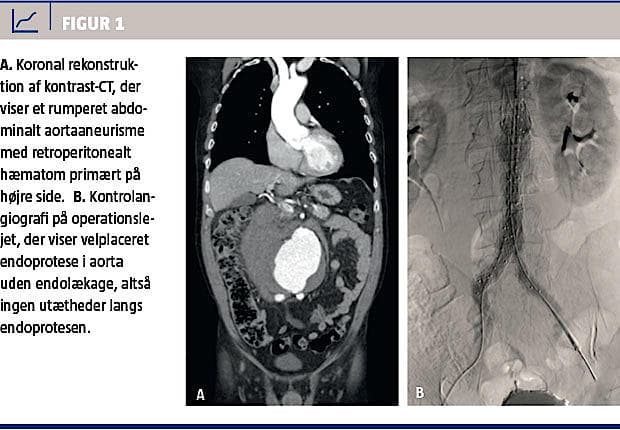

En akut CT med intravenøs kontrast afslørede et 9,4 cm bredt, infrarenalt RAAA (Figur 1A). På baggrund af de anatomiske forhold fandtes det pågældende RAAA egnet til endovaskulær behandling. På en hybridstue (dvs. en operationsstue, hvor der også er mulighed for radiologisk intervention) implanterede man i lokal anæstesi via begge lysker en aorto-biiliakal endoprotese (Figur 1B). Postoperativt kunne patienten mobiliseres efter få timer. Der var normal fodpuls bilateralt og ingen tegn på hæmatomer i

lyskerne, intraabdominalt kompartment, nyrepåvirkning eller tarmiskæmi. Det primære indlæggelsesforløb varede ni dage og var forlænget på grund af intravenøs antibiotisk behandling for pneumoni. Tre dage efter udskrivelsen blev patienten genindlagt pga. trombosering af venstre endoproteseben, der ikke kunne genåbnes, og der blev derfor anlagt en crossover-bypass fra højre a. femoralis til venstre a. fe-

og afløbskarrene til venstre ben. Efter yderligere ti dages indlæggelse kunne han udskrives uden varige men. En kontrol-CT tre måneder postoperativt viste tilfredsstillende placering af endoprotesen og reduktion af aneurismediameteren til 7,5 cm. Der var ingen endolækage